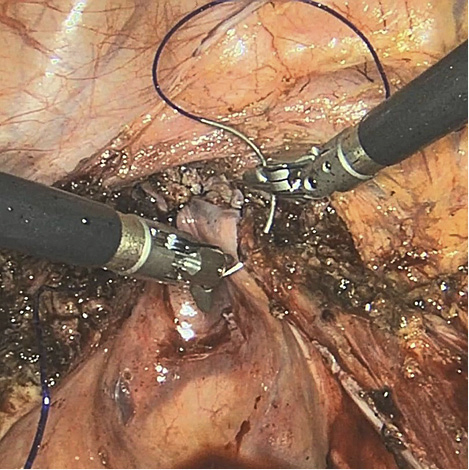

two-19.jpg

Figure 4. Suturing with two robotic needle holders